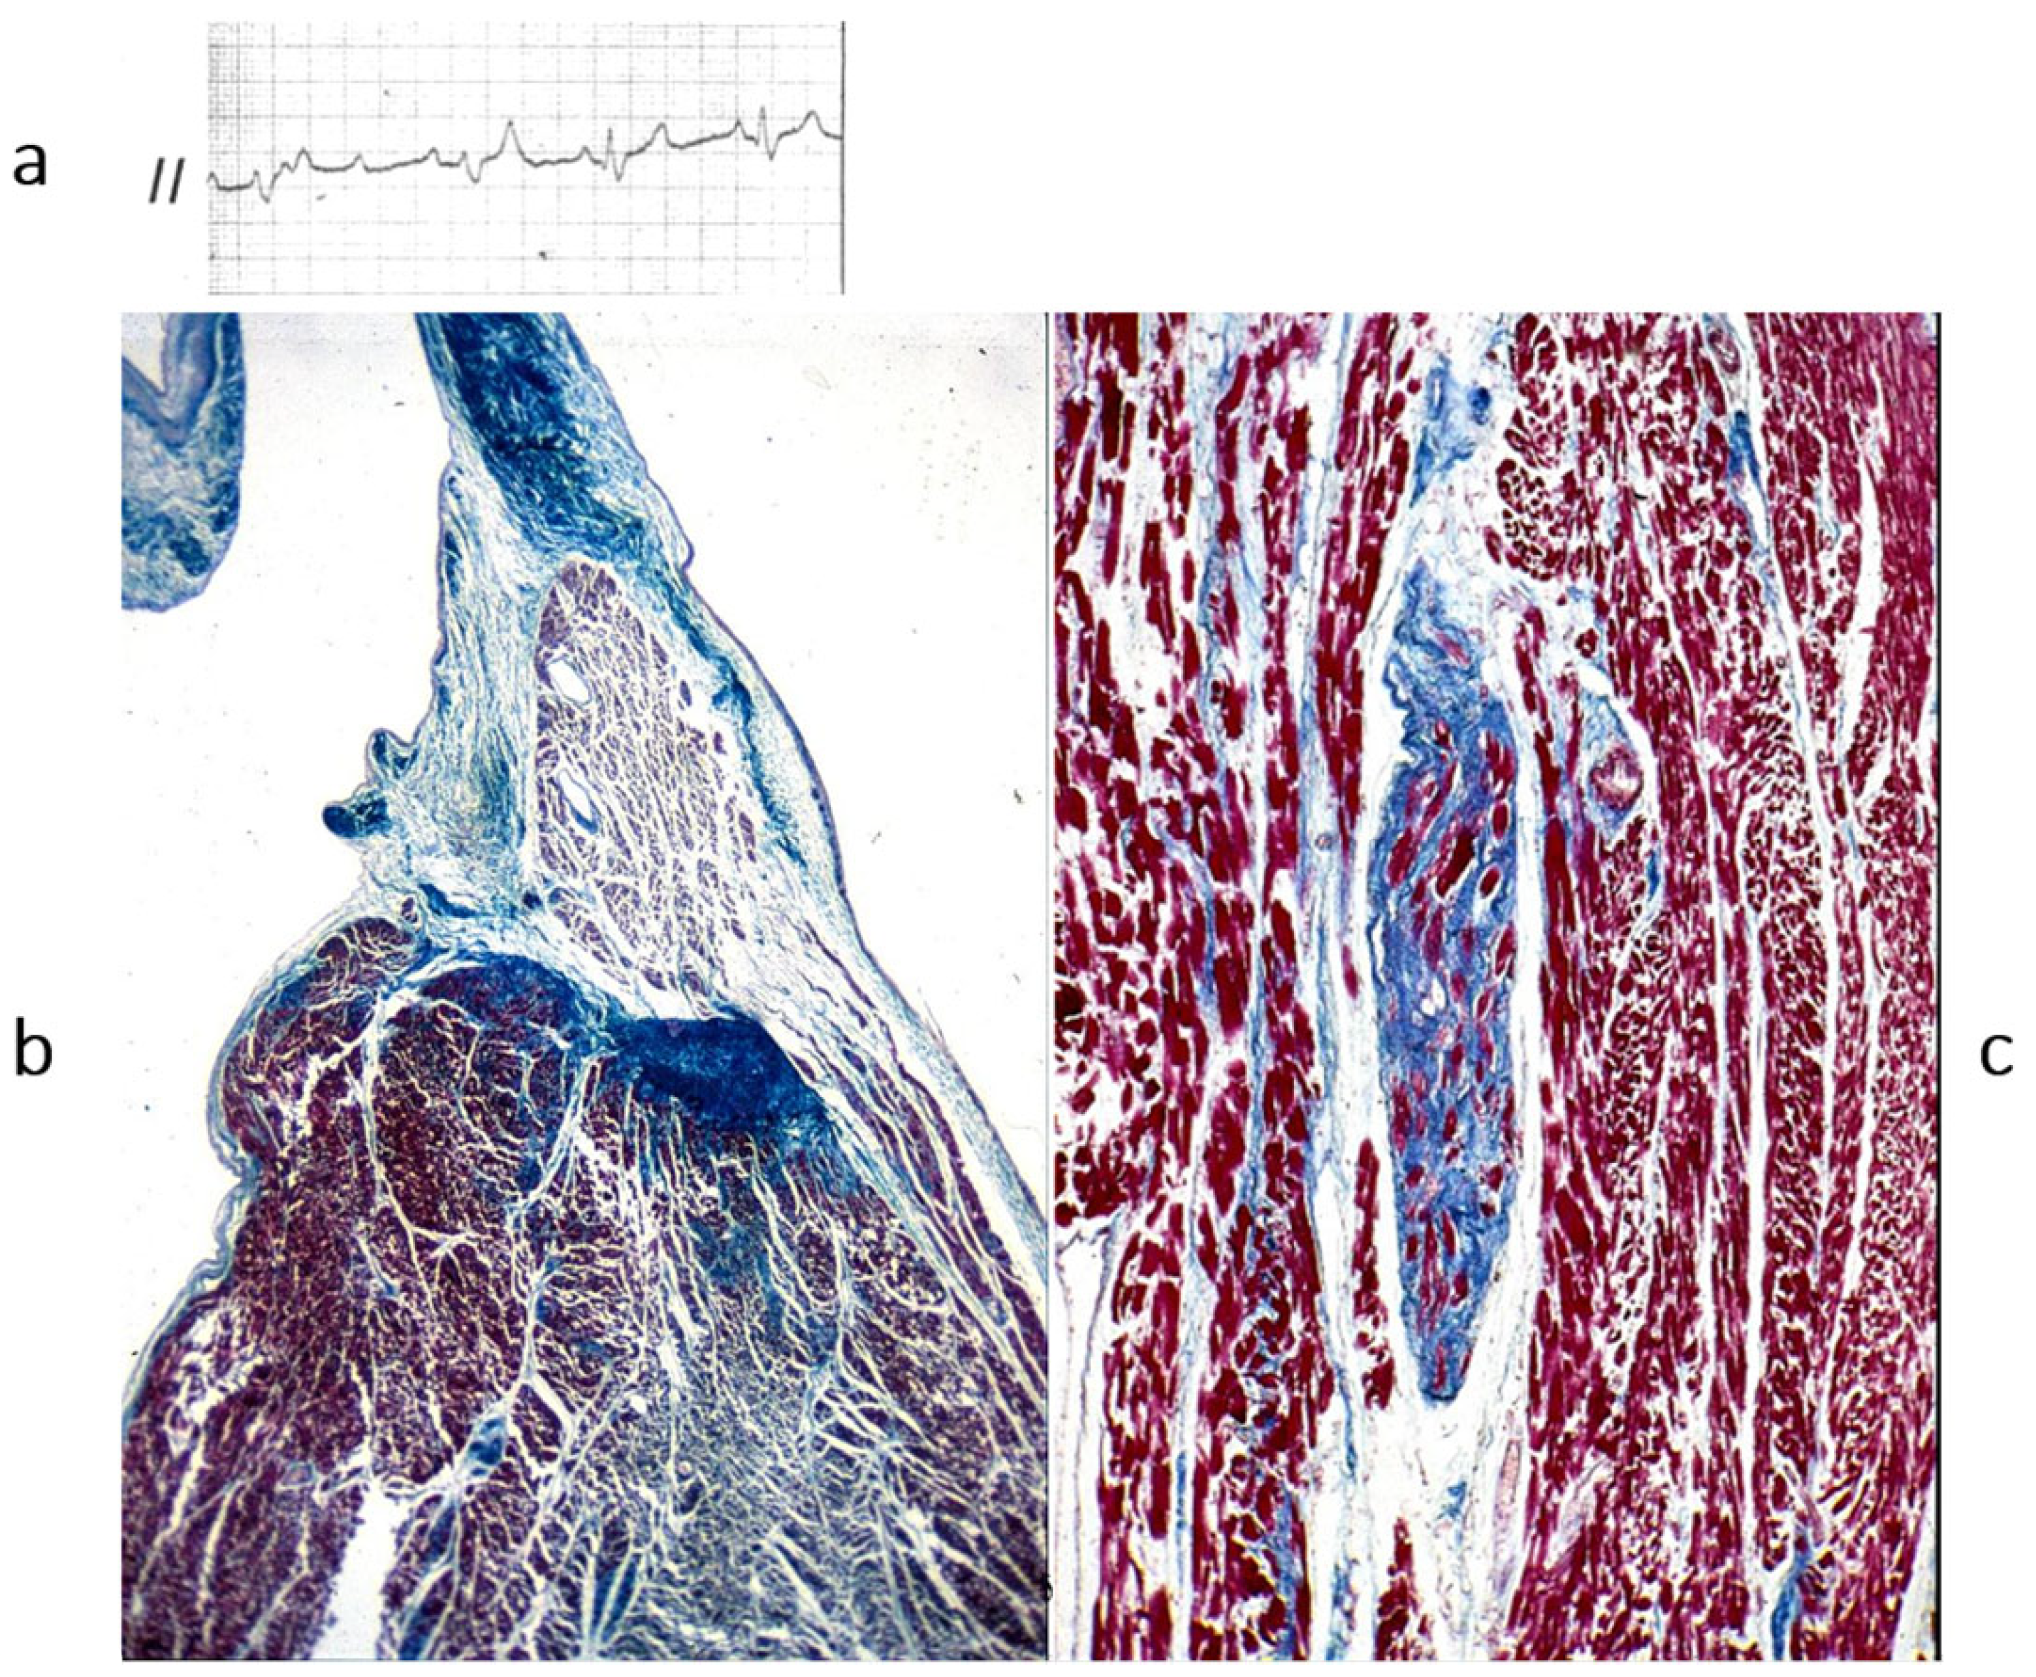

Also, complete AV block may be inherited, with the name of Lenegre disease (Figure 21).

Thus, mutations of sodium “channel I5” account for long QT, Brugada syndrome and Lenegre disease. The latter is an example of a genetically determined cardiomyopathy of the conduction tissue (Figure 21).

Figure 21. Also, AV block may be to a sodium channelopathy. (a) AV block on ECG; (b) fibrotic disruption of bundle of His bifurcation; (c) right bundle branch is replaced by fibrosis. Azan Mallory stain. The inherited AV block of Lenegre should be considered a cardiomyopathy of the conduction system. From [4] with permission.